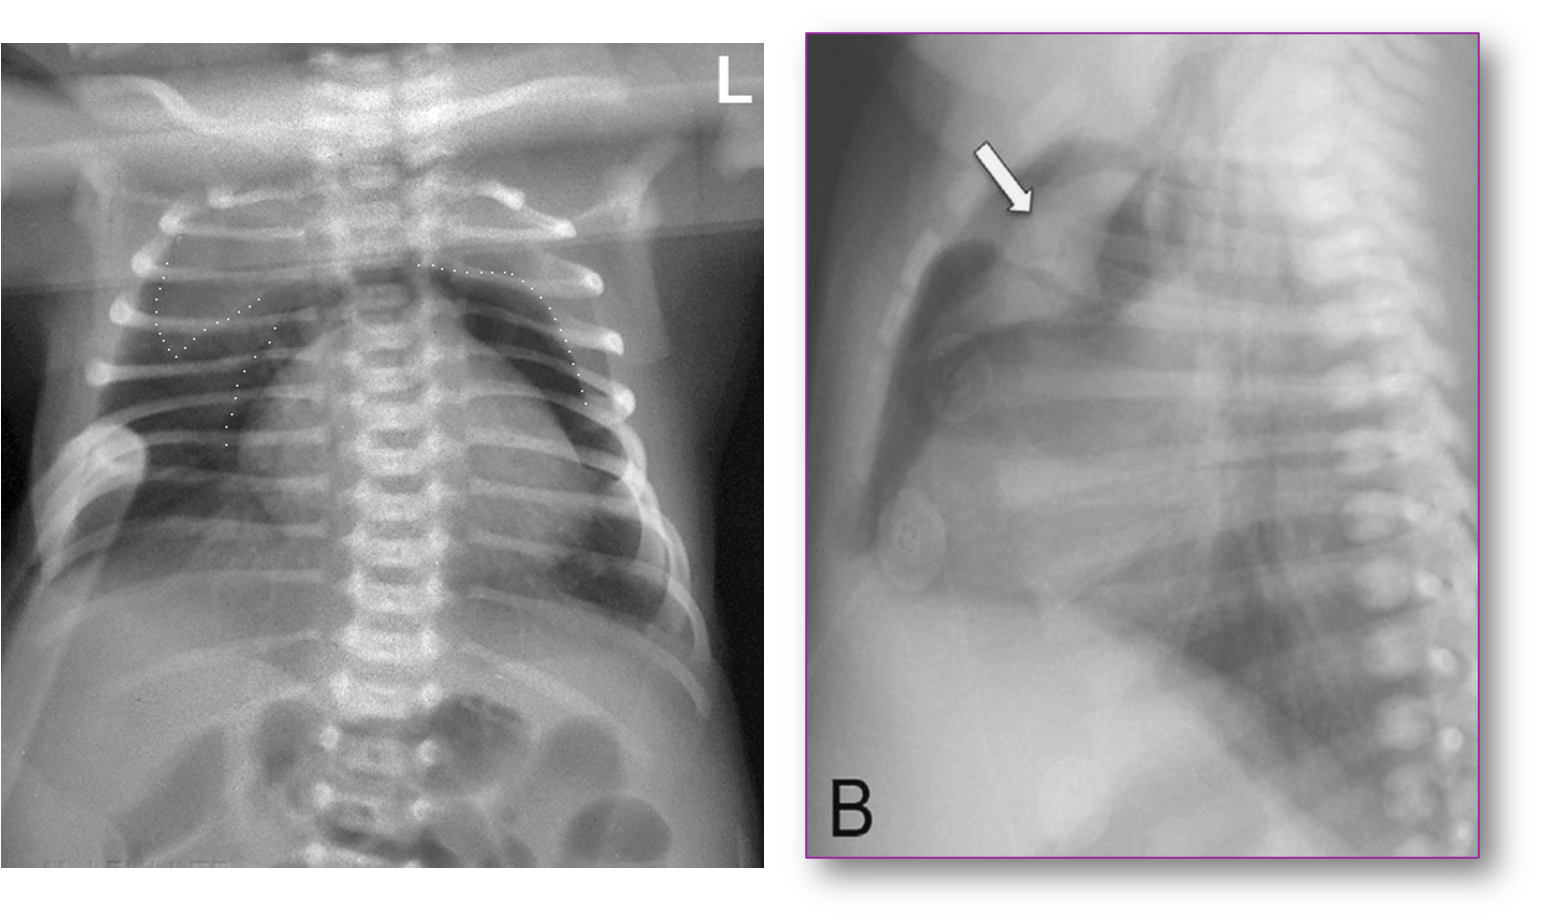

Newborn with Mild Respiratory Distress

Had pneumomediastinum elevating the thymus “spinnaker sail” sign.